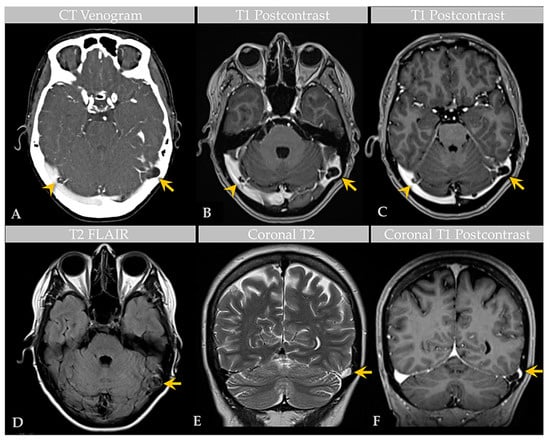

2.2. Imaging Features

A recent MRI exam of the brain, performed at an outside institution, was interpreted as positive for bilateral transverse sinus thrombosis. The patient was transferred to our institution and underwent computed tomography (CT) venogram of the head (Figure 1). CT venogram analysis and reinterpretation of the brain MRI revealed bilateral GAGs that impinged on the lateral transverse sinuses (TS). The GAGs measured 1.1 cm on the right side and 1.6 cm on the left side and demonstrated a heterogeneous T2 signal (Figure 1). A third GAG that measured 1.5 cm and was sessile in morphology was also identified along the superior sagittal sinus (SSS). There was no TS or other DVS thrombosis.

Figure 1. Case 1: Imaging of an individual with multiple GAGs. CT venogram (A) shows GAGs indenting the lateral aspect of bilateral TS (arrow, arrowhead). Postcontrast T1-weighted MRI images (B,C) demonstrate bilateral TS GAGs, measuring 1.6 cm on the left (arrow) and 1.1 cm on the right (arrowhead). The GAG is associated with focal severe narrowing of the lateral left TS (arrow, (C)). Axial T2-weighted FLAIR image (D) demonstrates heterogeneous signal within the GAG (arrow), likely reflecting internal soft tissue elements with CSF flow turbulence. Coronal T2-weighted (E) and postcontrast T1-weighted (F) images show high-grade TS luminal narrowing by the GAG (arrows). An additional SSS GAG is not depicted.